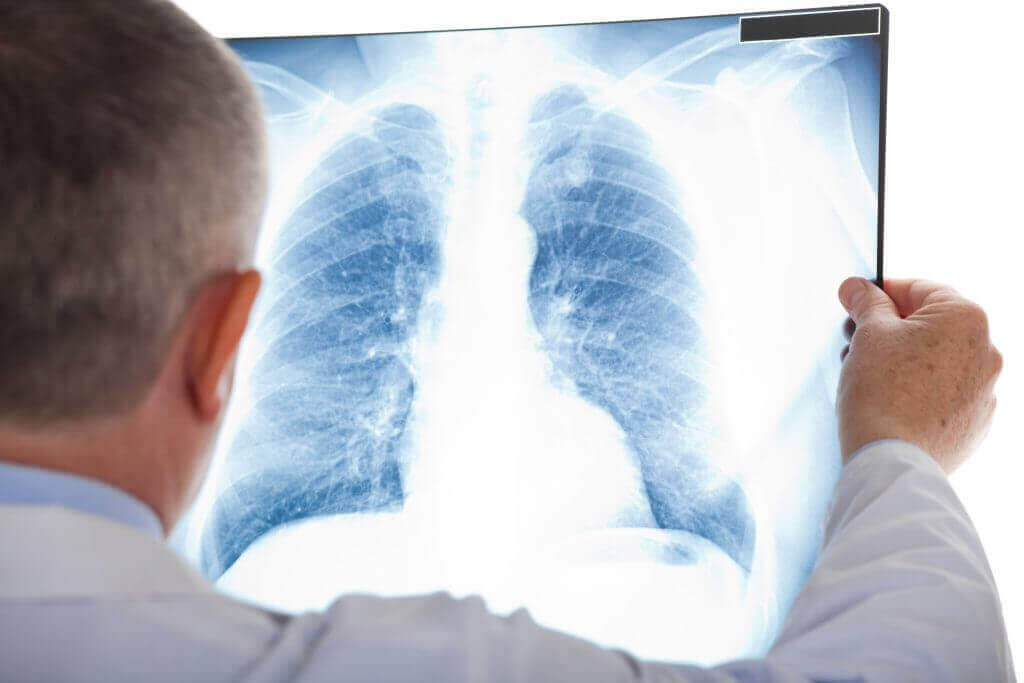

Om atelectase te diagnosticeren, is een gedegen klinische verkenning en een röntgenfoto meestal voldoende. Toch kunnen artsen een reeks technieken gebruiken om de diagnose te bevestigen of de ernst ervan te bepalen.

Deze technieken omvatten een CT-scan (computertomografie), bronchoscopie, echografie en oximetrie (Spaanse link). In feite maakt bronchoscopie het mogelijk om obstructies te observeren en zelfs blokkades op te heffen.